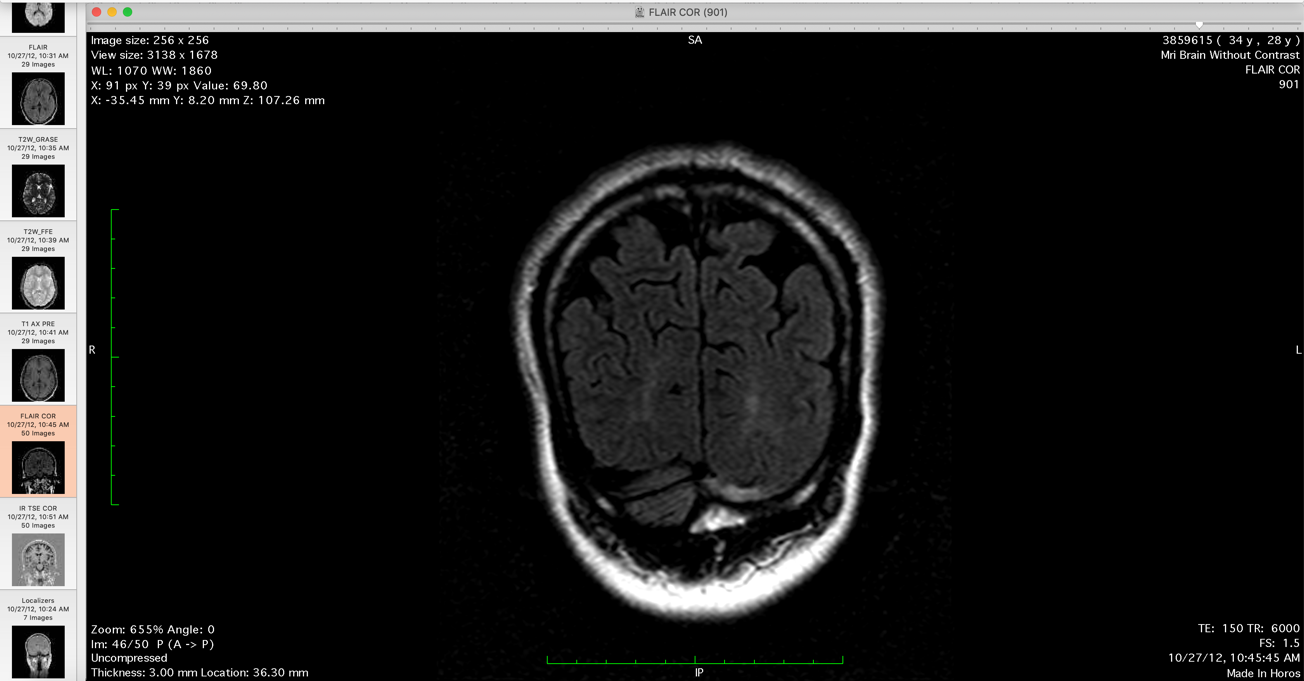

Pia: So you have MRI scans with you?

Me: Yup I have the MRI scans with me.

Me: There is a usually a massive headache there are lesions in the upper cervical column at that point and that would create both the headaches and then nausea vomiting and then there are peripheral pains which can become excruciating. Its almost unbearable at that point so. I have some of the MRI examples, there are actually quiet a few.

Me: So, I did it specifically to show relapse and remission and then I had the radiologist do a comparison.

So that shows posterior brain [lesions], and you can see.... Its mostly the occipital region. And what typically happens is that.... if

Pia: So where is the lesion?

[these are the clear lesions shown to Dr. Pia, which he deludedly professes not to be able to see its clinical fraud in statement]

Me: Keep going back. So there you go, these intensities here.

Pia: Lets look at the transversal slides.

Me: Its depends on the, what I did is that I had the radiologist do a comparison of the different MRIs and then he noted where these intensities.

Pia: So these are the newest ones.

Me: No these aren't the newest.

Pia: Show me the newest.

Me: So, this is the new, newer. This would show the posterior intensity sometime it will show some central intensity....

Pia: Contrast enhanced in any one of time? [Dr. Pia makes a misstatement]

Me: Hmm, they have. The contrast is the T1 images hmm, but....

Pia: Do you have any spinal lesions?

Me: Yup, I do as well. I have the spinal MRI, just have to move the mouse to the right.

He compared 4 brain MRIs in this series. He compared the MRI with the 2012 MRI and then 2017. So he is basically comparing 4 MRIs the 20 and.... last year January that are no intensities in the occipital lobes as there are in the 2012 or in the 2....

Me: Otherwise there is change in the occipital lobe after the 2010. So these two MRI series here they both have signal intensity changes in the posterior part of my brain.

Pia: There is MR of the cervical and thoracic spine and there is no signs of demyelination.

Me: T2 inflammation only shows up in T2 images because you are subtracting the CSF fluid [from the image series]. So that is why they particularly show up in T2 flair images so you can see it quiet clearly here.

Me: But now quiet as well, so you can see intensities here. Etc. Etc. And these are fairly clear white matter intensities as well.